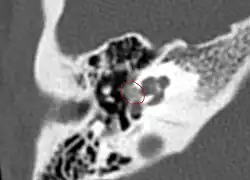

A high-resolution CT shows very subtle bone findings. However, CT is usually not needed prior to surgery.

Otosclerosis on CT can be graded using the grading system suggested by Symons and Fanning.[21]

Grade 1, solely fenestral;

Grade 2, patchy localized cochlear disease (with or without fenestral involvement) to either the basal cochlear turn (grade 2A), or the middle/apical turns (grade 2B), or both the basal turn and the middle/apical turns (grade 2C); and

CT scan of otosclerotic focus in the anterior footplateGrade 3, diffuse confluent cochlear involvement (with or without fenestral involvement).